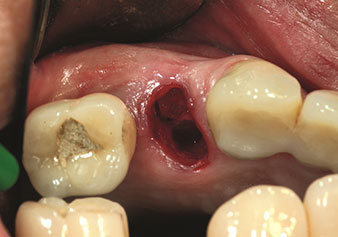

One application, which is often underestimated is the atraumatic extraction of tooth roots or root fragments in the scope of alveolar management. The fine periotomes, which are currently available in two versions (EX1 and EX2 from W&H), can also be used to remove teeth which have previously undergone special endodontic treatment or ankylosed roots with ease. This results in extraction alveoli where both the hard and soft tissue are fully intact as it is generally possible to avoid reflection.

This establishes the optimal basis for subsequent or immediate implant treatment (Figures 1 and 2 included with the kind permission of Dr Torsten Conrad, Bingen a. Rhein).

Situation following piezosurgical extraction

Fig. 2: Situation following piezosurgical extraction. Photo: © Dr Torsten Conrad (Bingen am Rhein)